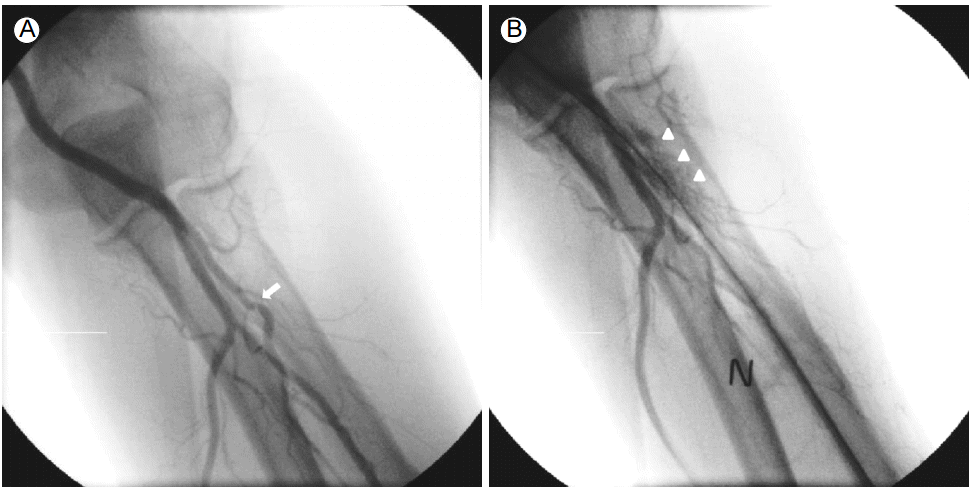

A 69-year-old male was hospitalized for coronary intervention after evaluation by computed tomography (CT) revealed critical stenosis of the distal left circumflex artery (LCX).The patient underwent coronary angiography via the left radial route with a 6 French (Fr) sheath (Terumo Corp., Tokyo, Japan) inserted using standard techniques. The left radial angiography showed a minor degree radial artery spasm (Fig. 1A). After injecting 200 μg of nitroglycerin via the radial artery, coronary angiography was successfully performed with 5 Fr JL4 and JR4 diagnostic catheters. The distal LCX lesion was similar to the lesion revealed by the coronary CT scan (Fig. 2A); therefore, PCI was deemed the best treatment option. During insertion of a 6 Fr extra back-up (EBU) guiding catheter (Medtronic, Dublin, Ireland) over a 0.035-inch standard guidewire, the catheter encountered resistance and the patient complained of pain in the left forearm. After removing the 6 Fr EBU guiding catheter, radial angiography was performed by injecting diluted contrast agent through the side port of the sheath. The contrast agent revealed perforation and extravasation of contrast agent into the surrounding tissue (Fig. 1B). A 5 Fr EBU was able to pass the perforated segment over the remaining 0.035-inch standard guidewire. PCI was performed successfully with balloon angioplasty and a 2.75 X 18-mm stent (Resolute integrity, Medtronic, Dublin, Ireland) (Fig. 2B). After removing the guiding catheter, radial angiography was performed via the sheath’s side port. The procedure showed that the perforation was sealed and that there was no contrast agent extravasation (Fig. 3).The patient was discharged after 48 hours without any local vascular complications, with a patent radial pulse, and no local hematoma.

Figure 1.

Baseline radial angiogram showing a minor degree spasm (arrow) (A). Perforation of the radial artery and extravasation of contrast agent into the surrounding tissue (arrowheads) (B). N, nitroglycerin.